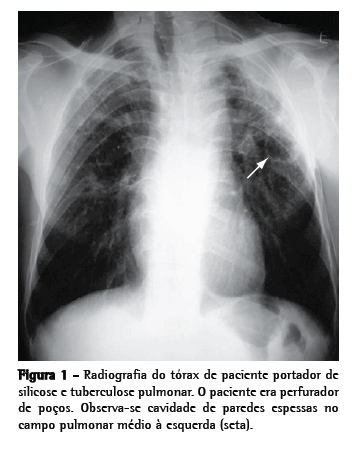

Como avaliação complementar inicial, recomenda-se realização de baciloscopia e cultura de escarro (induzido, se necessário, pois tem boa sensibilidade)(25) e radiografia de tórax(23,26) (Figura 1). Em caso de persistência de dúvidas quanto à presença de tuberculose ativa, pode-se lançar mão de broncoscopia com LBA, sempre que possível associado à biópsia transbrônquica; a realização de biópsias aumenta significativamente o rendimento ­diagnóstico do exame, mesmo nos doentes com pesquisa negativa para micobactérias no escarro e no LBA.(27)

Têm sido reconhecidos também padrões sugestivos de silicotuberculose na TC de tórax. Os principais achados compatíveis com tuberculose ativa sobreposta à silicose são cavitações de paredes espessadas, consolidações, imagens com aspecto de árvore em brotamento, assimetria das imagens nodulares e progressão rápida da doença(26,28,29) (Figura 2).